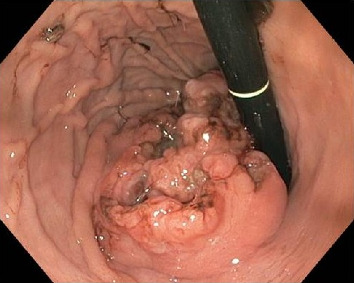

Up to one-third of germ cell tumors are extragonadal neoplasms, with yolk sac tumors (YSTs) being the most common malignant histology. This report describes the successful multimodal management of a primary YST of the stomach in a 2-year-old boy. The child presented with melena, and further evaluation revealed a mass lesion in the cardia of the stomach. A biopsy established a diagnosis of a YST, which correlated with an elevated serum alpha-fetoprotein level. The child received three cycles of chemotherapy consisting of cisplatin, etoposide, and bleomycin (PEB), followed by surgical resection in the form of proximal gastrectomy. After an uneventful recovery from surgery, he received an additional three cycles of PEB and has remained disease-free for 7 years. This case highlights the potential for the occurrence of a relatively rare childhood tumor at an unusual site, which can pose diagnostic challenges. However, careful evaluation and meticulous management can lead to favorable outcomes.